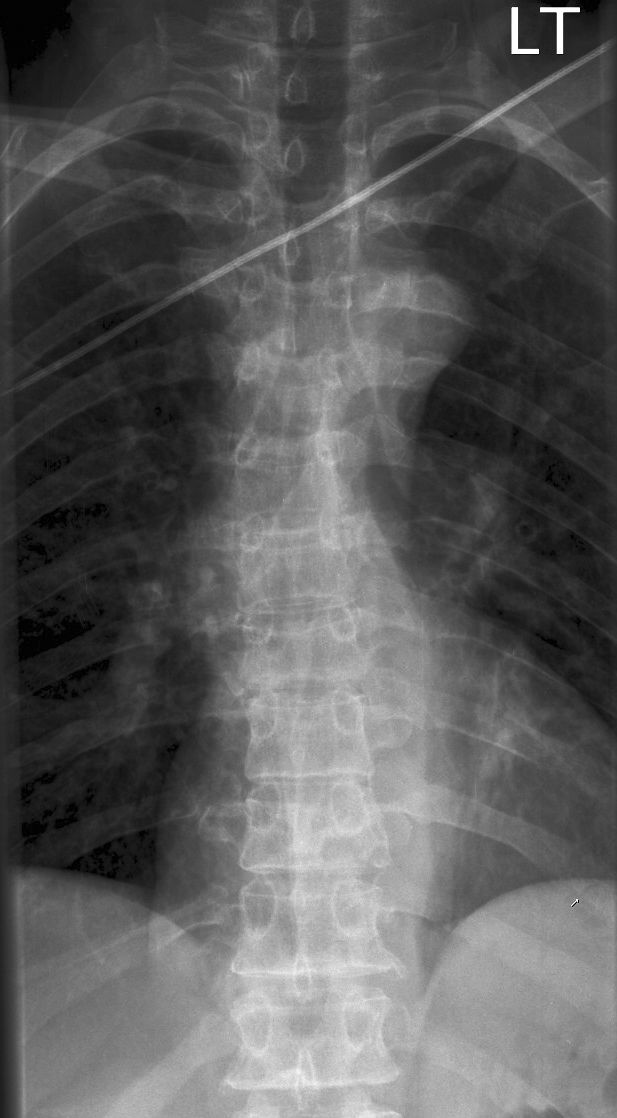

Gallery Blunt Chest Trauma Spine trauma Case 2b

Case 2b